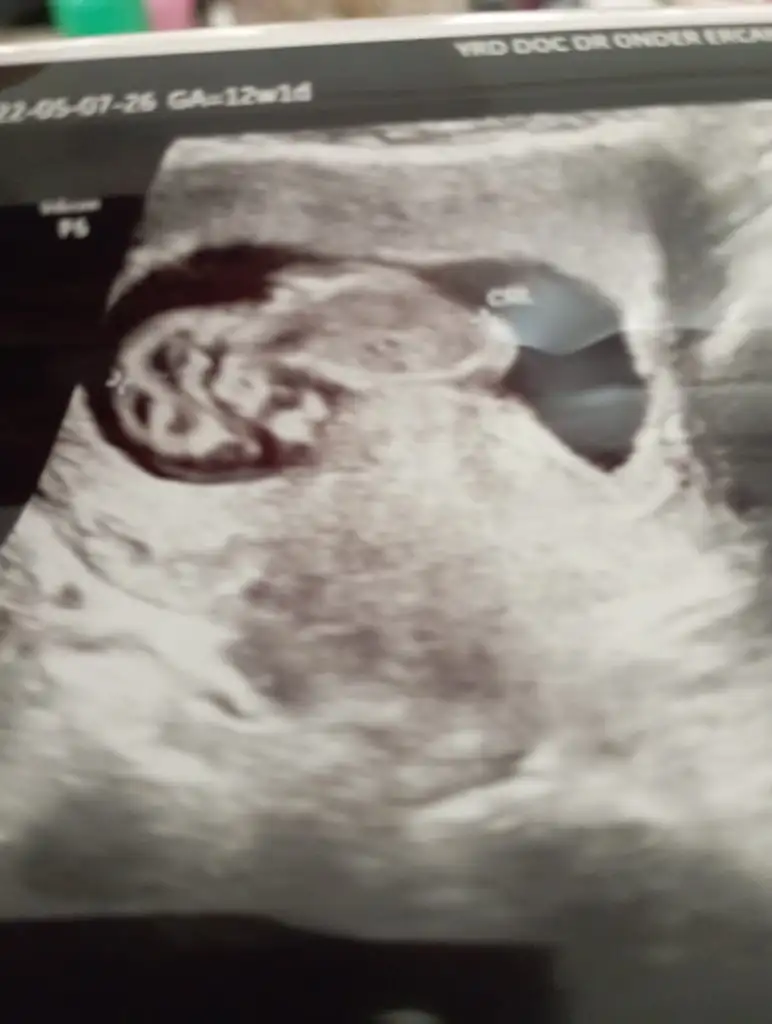

Merhaba Pasha22 Pasha22 acaba bana da yorum yapabilir misiniz? Merakla bekliyorum cinsiyeti.

Ilk foto 13+4

2.foto 11+5